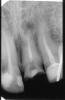

Hercule Опубликовано 25 ноября, 2012 Поделиться Опубликовано 25 ноября, 2012 (изменено) Здравствуйте!Год назад сломался передний зуб и на снимке обнаружили кисту.26 Апреля 2012 года была проведена резекция корня.3 Июля сделана 3Д томограмма Planmeca_Romexis_Viewerвот тут её можно скачать.http://files.mail.ru/697LNM Подскажите, пожалуйста, всё ли там хорошо в районе 1-го справа.Ничего не болит, только едва заметно периодически отекает И что можно сказать по поводу правой гайморовой пазухи. Вопросы всвязи с тем, что не могут ли эти места быть источником хронической инфекции.У меня хронический гастрит, хронический панкреатит и подозрение на хронический миокардит. Спасибо! Изменено 25 ноября, 2012 пользователем Hercule Ссылка на комментарий

Hercule Опубликовано 25 ноября, 2012 Автор Поделиться Опубликовано 25 ноября, 2012 28 ноября :Апрель перед резекцией:Май после резекции:Июль после резекции: Скриншоты от 3Д Ссылка на комментарий